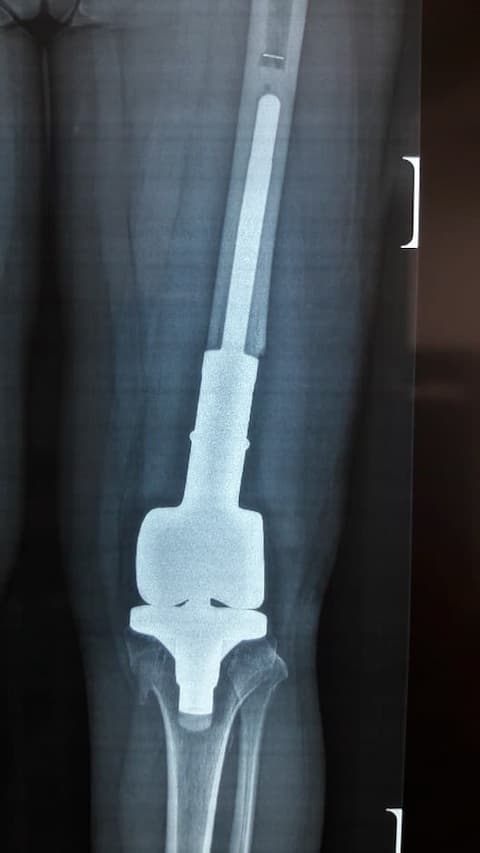

Үе дайрсан ясны анхдагч хавдар, ясны дутмагшлын үед хийгдэх мэс засалimg20Үе дайрсан ясны анхдагч хавдар, ясны дутмагшлын үед хийгдэх мэс засалimg21

Зураг 3. Мэс заслын дараах рентген зураг. Эгц урд, хажуугаас авсан байдал

Энэ тохиолдолд үений шөрмөсөн холбоос хэвийн хадгалагдаж үлдсэн байсан. Хиймэл үе - ястай тогтвортой сайн бэхлэгдэх нөхцлийг хангах чөмөгт гол руу орсон уртасгагч – extension stem-тэй хиймэл үе.